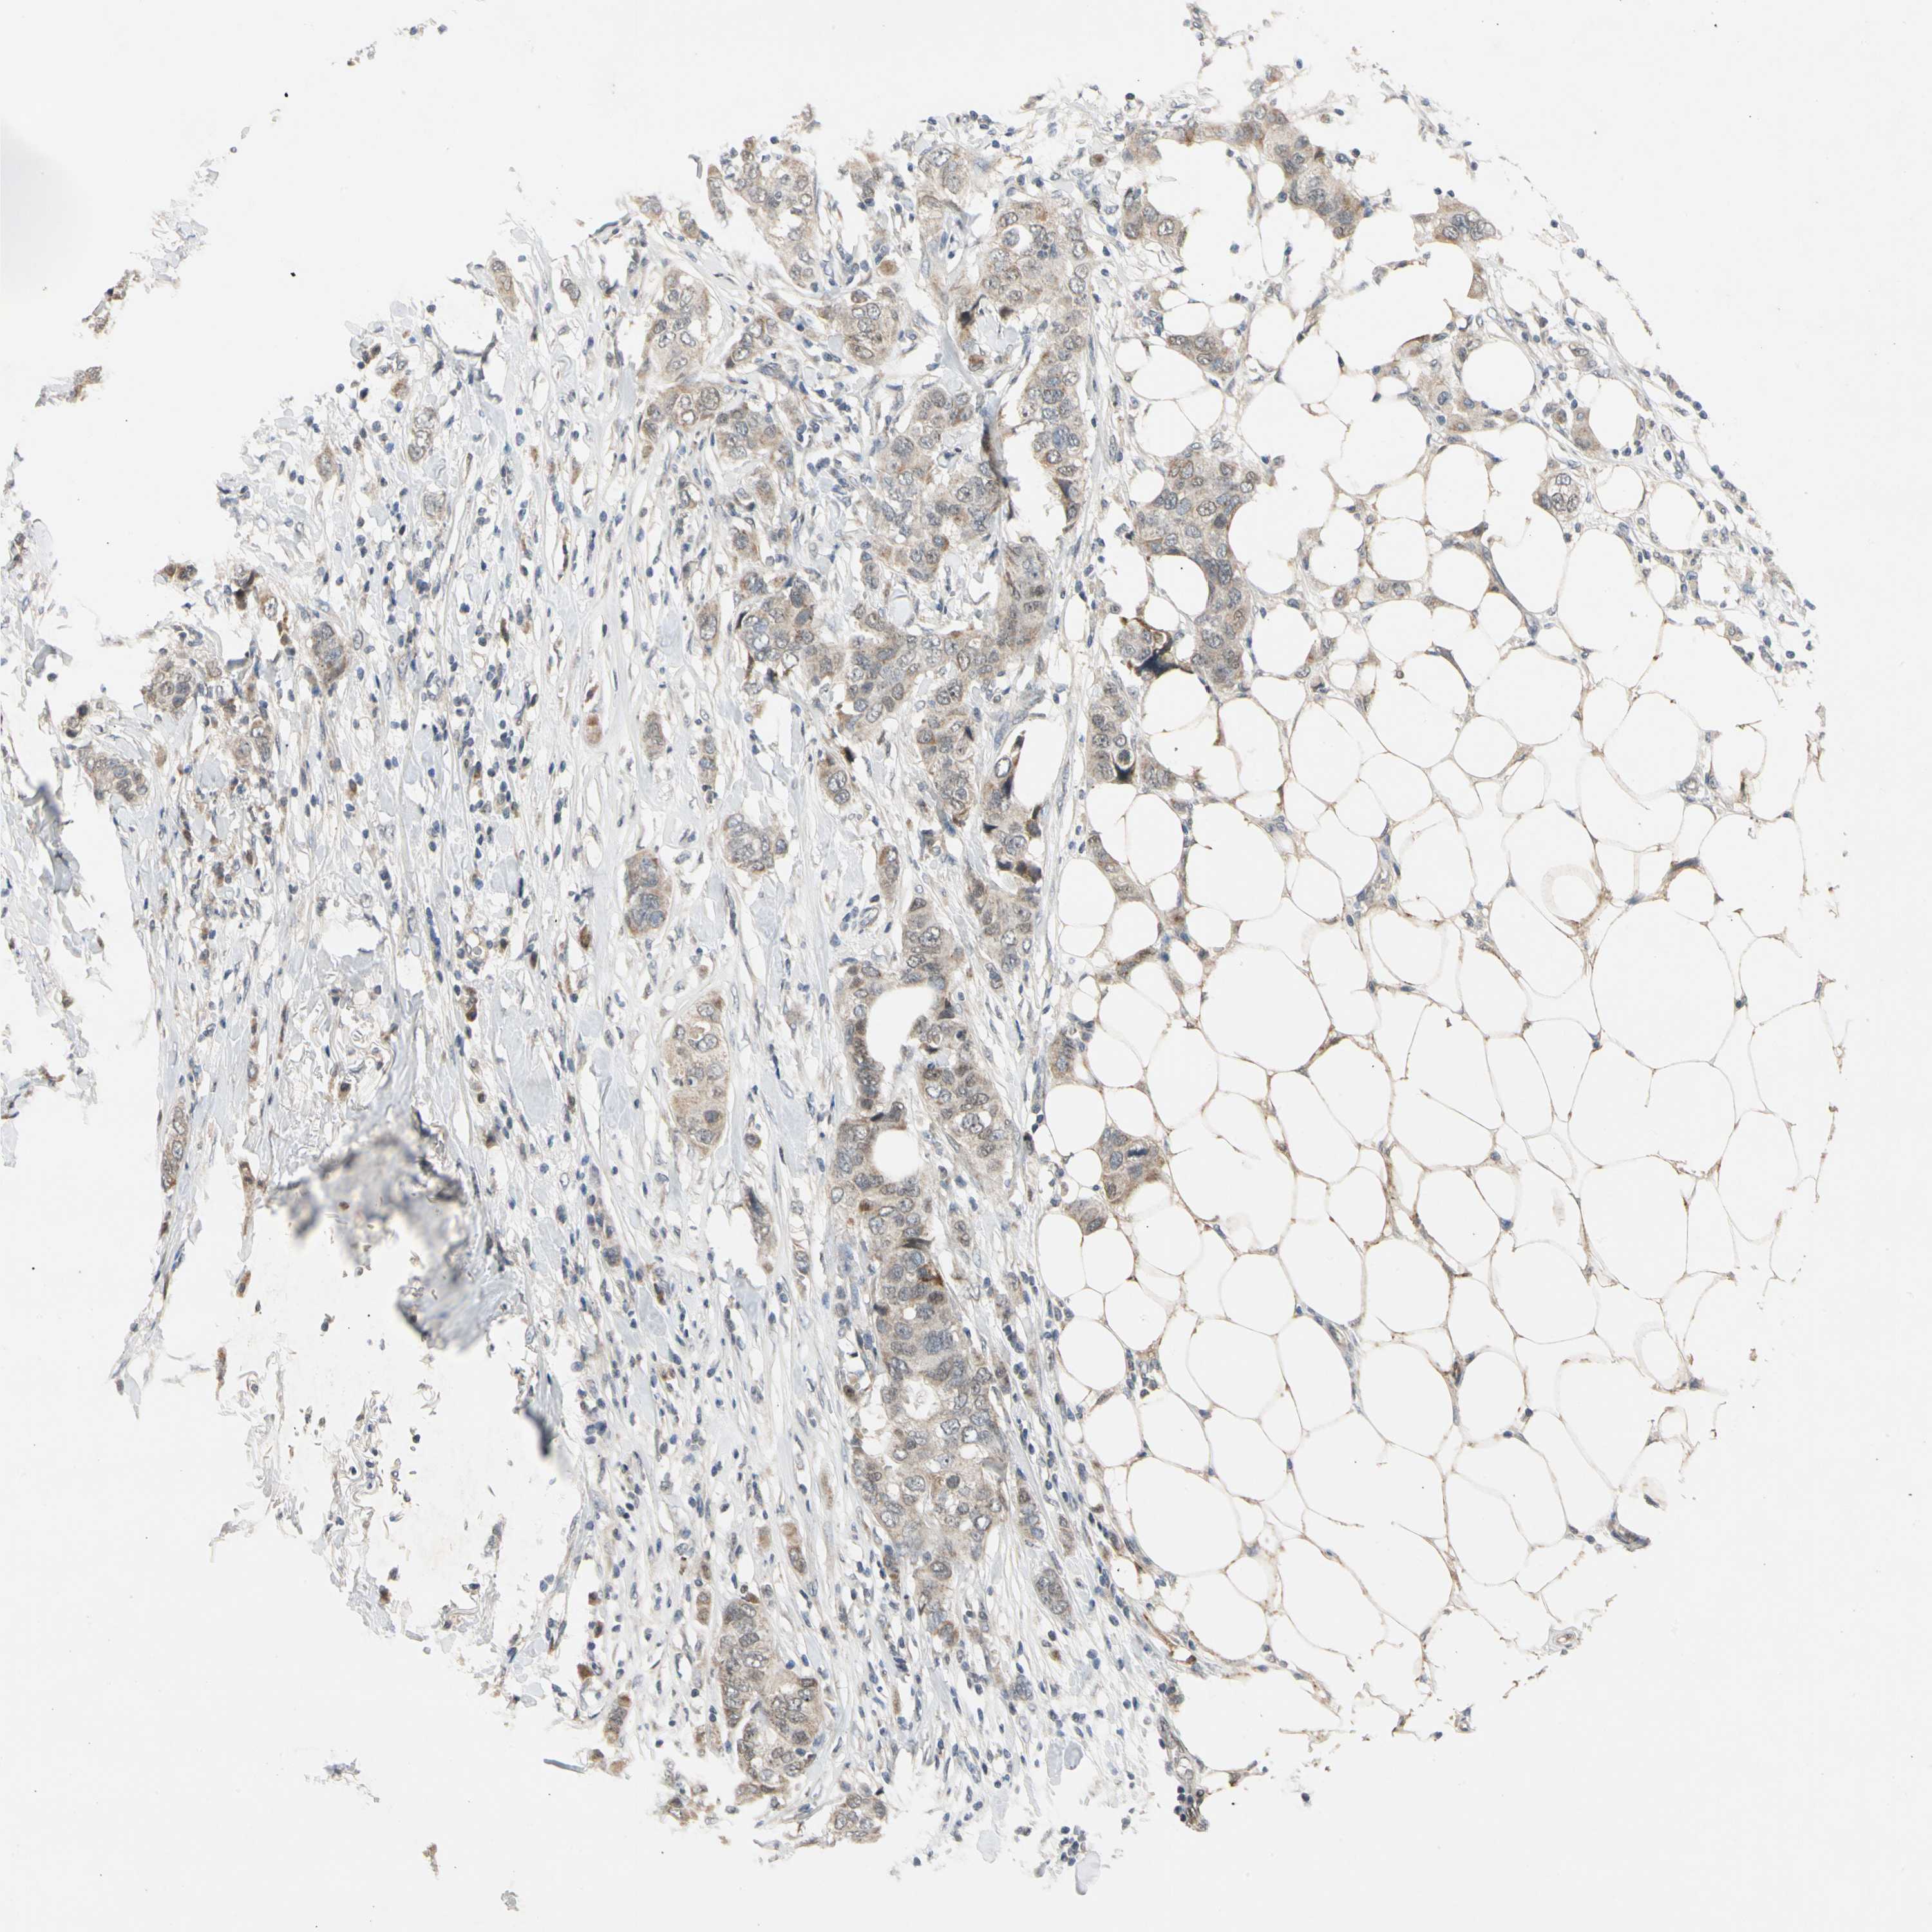

BRCA TCGA BRCA VALIDATION PROTEIN EXPRESSION